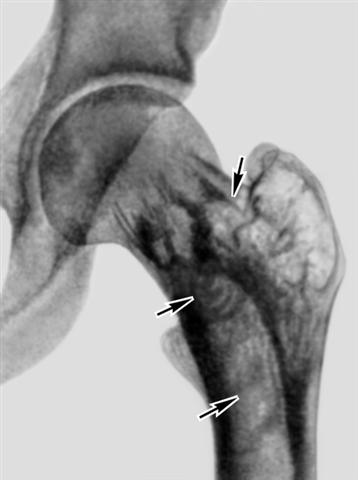

Рис. 1. Рентгенограмма левого тазобедренного сустава больного с болезнью Педжета: структура межвертельной области бедренной кости имеет грубый вид, ячейки (указаны стрелками) между костными перекладинами крупные, неправильной формы.